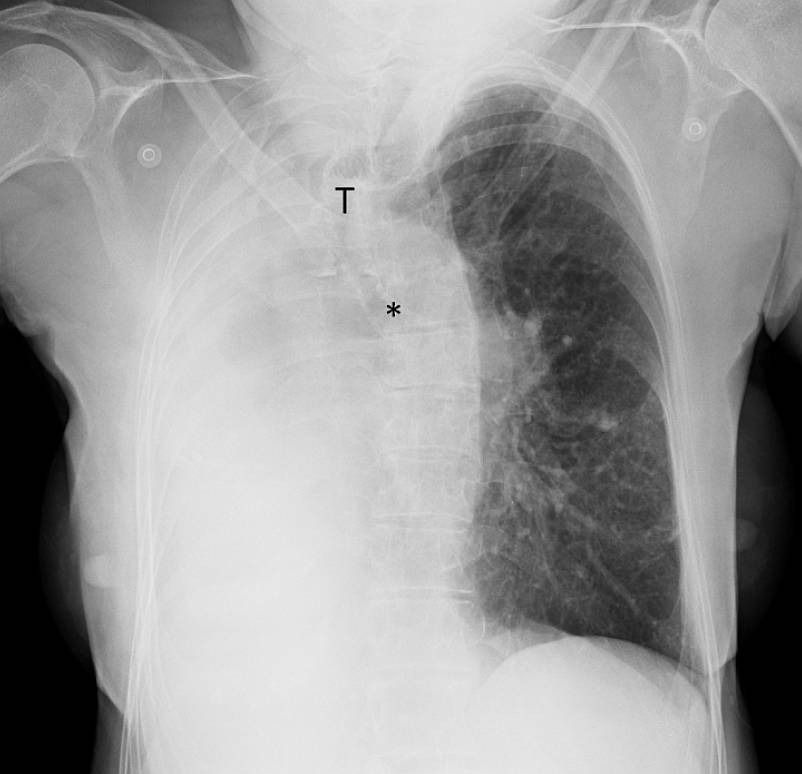

Chest radiography performed at emergency department revealed an opaque right hemithorax and a mediastinum entirely displaced to the right side. The trachea was also displaced to the right and the left main bronchus is depicted; however, the right main bronchus is not seen.

The right intercostal spaces seem reduced relatively to the left ones, indicating volume reduction; the left lung appears radiolucent due to compensatory overinflation.

Imaging studies are essential for the diagnosis of pulmonary agenesis. The diagnosis is usually first suspected on chest radiography, which demonstrates a diffuse opacity of the affected hemithorax and an ipsilateral mediastinal shift [1, 6, 8]. A normal contralateral lung with compensatory hyperinflation and herniation across the midline is a common finding [6]. CT confirms the absence of lung parenchyma, pulmonary artery, and bronchial structures on the affected side [4, 6, 7]. CT angiography and MR angiography are currently the imaging modalities of choice in the diagnosis of this entity [6].